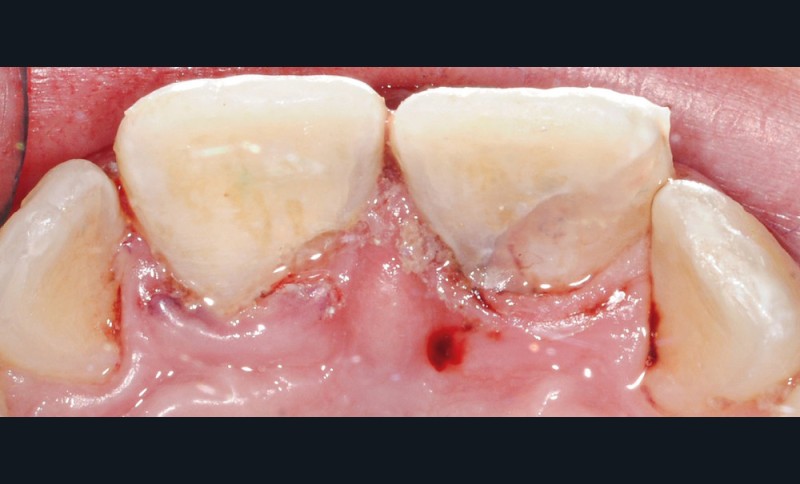

- une fracture corono-radiculaire avec effraction pulpaire de 11 et 21 (fig. 1 et 2) ;

- une subluxation de 11 et 21 (saignements sulculaires).

Les fragments sont placés dans du sérum physiologique afin de les réhydrater et d’augmenter leur potentiel d’adhésion. Dans un premier temps, des anesthésies locales en para-apicale de 11 et 21 sont réalisées. Des anesthésies de contact à l’aide d’un gel lidocaïné ou d’une cryoanesthésie peuvent être faites en amont pour diminuer les sensations désagréables de l’anesthésie locale. L’étape suivante consiste en la mise en place du champ opératoire. Au niveau du secteur antérieur, la mise en place d’une feuille de digue maintenue par des cordonnets élastiques de stabilisation (Wedjet™) est souvent réalisable. Sa mise en place est rapide et évite la pose d’un crampon sur des dents impliquées dans le traumatisme. Un crampon sur la 55 est également placé afin de maintenir la digue. L’étanchéité obtenue n’est pas toujours idéale et des spécificités liées à l’enfant compliquent sa mise en place, comme ici des dents malpositionnées ou en cours d’éruption (fig. 4). Après un nettoyage des dents fracturées et des fragments à replacer, une vérification du repositionnement correct de ces fragments est effectuée. Une pulpotomie partielle d’une profondeur d’un millimètre est réalisée sur la 11 à l’aide d’une fraise boule diamantée. Un biomatériau de type biocéramique (Biodentine™) vient coiffer la pulpe de 11 et 21 (fig. 5). Les bords amélaires sont ensuite soigneusement nettoyés à l’aide d’une microbrossette. En effet, l’adhésion se fera principalement entre l’émail de la dent fracturée et l’émail du fragment. L’épaisseur de biocérmique est réduite pour être la plus fine possible.